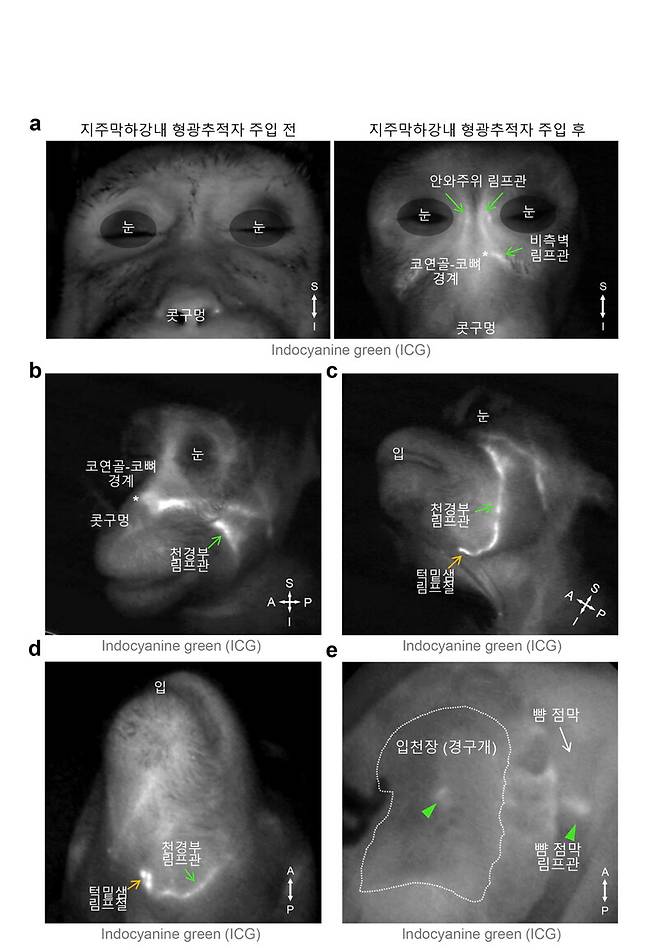

연구진은 이번 생쥐 실험에서 피부에 좀 더 가까운 배출 경로를 새롭게 알아냈다. 뇌척수액에 형광 염료를 넣어 살펴본 결과, 뇌척수액이 눈 주위와 코 안쪽, 입천장 림프관을 통해 눈, 코 옆쪽 얼굴 피부 아래의 림프관으로 모인 뒤 턱밑샘 림프절로 배출되는 걸 확인했다.

진호경 선임연구원은 “한국생명공학연구원 국가영장류센터를 통해 이 경로가 생쥐뿐 아니라 영장류에도 존재한다는 걸 확인했다”고 말했다. 이는 사람에게도 비슷한 뇌척수액 배출 경로가 있을 가능성이 크다는 걸 시사한다.